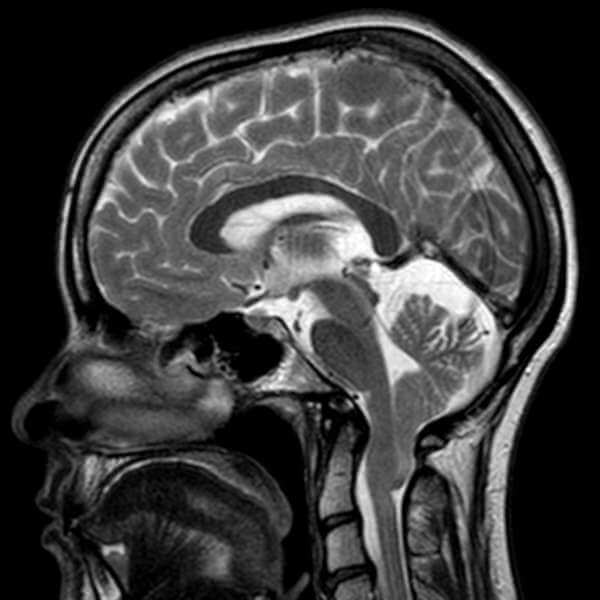

Chiari Τύπου Ι

Γυναίκα ασθενής 31 ετών, με ιστορικό πονοκεφάλων από πολλών ετών, με προοδευτική επιδείνωση της συμπτωματολογίας και επιπλέον ίλιγγο με δυσκαταποσία και αστάθεια βάδισης. Στο πλαίσιο της διερεύνησης με μαγνητική τομογραφία εγκεφάλου διαπιστώθηκε παρουσία δυσπλασίας Chiari τύπου Ι με εγκολεασμό των αμυγδαλών της παρεγκεφαλίδας και συμπίεση του προμήκη μυελού και του νωτιαίου μυελού στο ύψος της κρανιοαυχενικής συμβολής. Εξαιτίας της συμπτωματολογίας και του προχωρημένου ακτινολογικού ευρήματος τέθηκε η χειρουργική ένδειξη της αποσυμπίεσης του ινιακού τρήματος μέσω μικρής κρανιεκτομής και πεταλεκτομής του πρώτου αυχενικού σπονδύλου, μερική αφαίρεση των αμυγδάλων, λύση των χρόνιων αραχνοειδικών συμφύσεων και μηνιγγοπλαστική. Η επέμβαση διενεργήθηκε υπό ολική νάρκωση, χωρίς επιπλοκές, και η ασθενής μετά από 4ήμερη νοσηλεία πήρε εξιτήριο. Τα συμπτώματα παρουσίασαν ταχεία βελτίωση. Η μετεγχειρητική μαγνητική δείχνει πλήρη αποσυμπίεση των νευρικών δομών με παρουσία ικανού υπαραχνοειδούς χώρου γύρω από το μυελό.